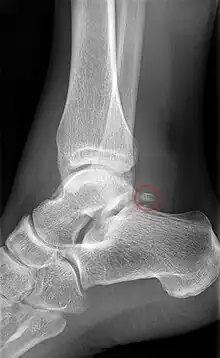

Ankle

Accessory bones of the ankle.[13]

Accessory bones at the ankle mainly include:

• Os subtibiale, with a prevalence of approximately 1%.[14] It is a secondary ossification center of the distal tibia that appears during the first year of life, and which in most people fuses with the shaft at approximately 15 years in females and approximately 17 years in males.[14]

• Os subfibulare, with a prevalence of approximately 0.2%.[15]

Os trigonum (further described below) may also be seen on an ankle X-ray.

The os trigonum or accessory talus represents a failure of fusion of the lateral tubercle of the posterior process of the talus bone. Is estimated to be present in 7–25% of adults.[17] It can be mistaken for an avulsion fracture of lateral tubercle of talus (Shepherd fracture) or a fracture of the Stieda process. In most cases, Os Trigonum will go unnoticed, but with some ankle injuries it can get trapped between the heel and ankle bones which irritates the surrounding structures, leading to Os Trigonum Syndrome.[21]